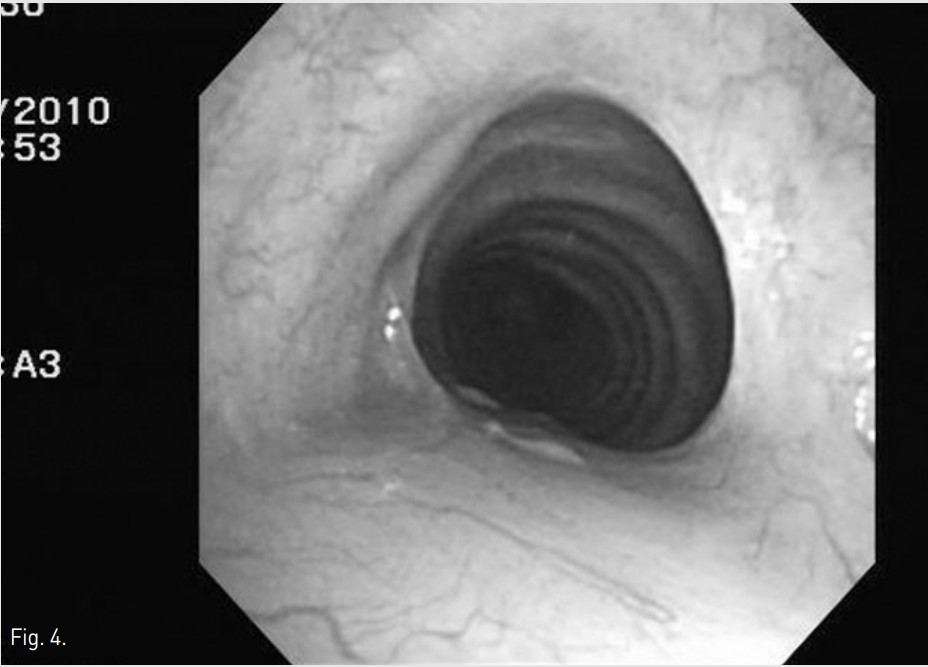

Fig. 4.

Fig. 4 Bronchoscopic image obtained 3 months after balloon dilation shows widening of tracheal lumen with multifocal healing scars at same level.